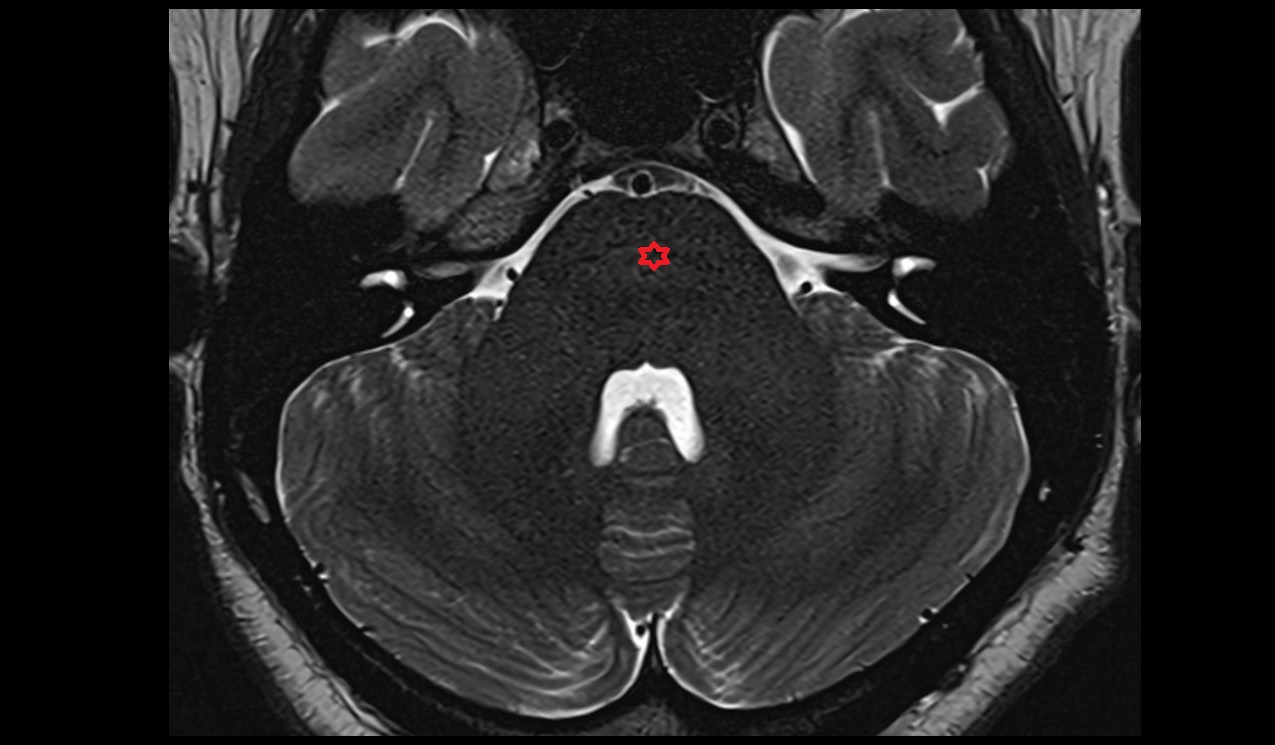

- Hippocampus